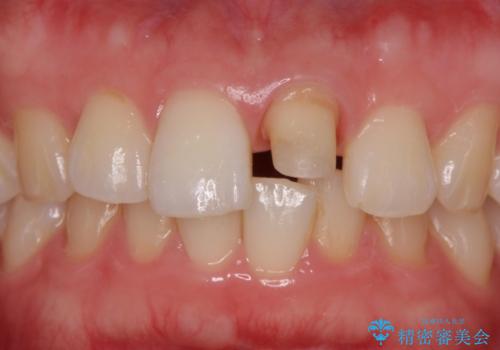

前歯の変色とガタつき ジルコニアクラウンでの修復

- 前歯の変色とガタつきが気になるとのことで来院された患者様です。

根管治療からやり直しを行った後、ジルコニアクラウンで修復することで、ガタつきと変色の両方を改善していきます。